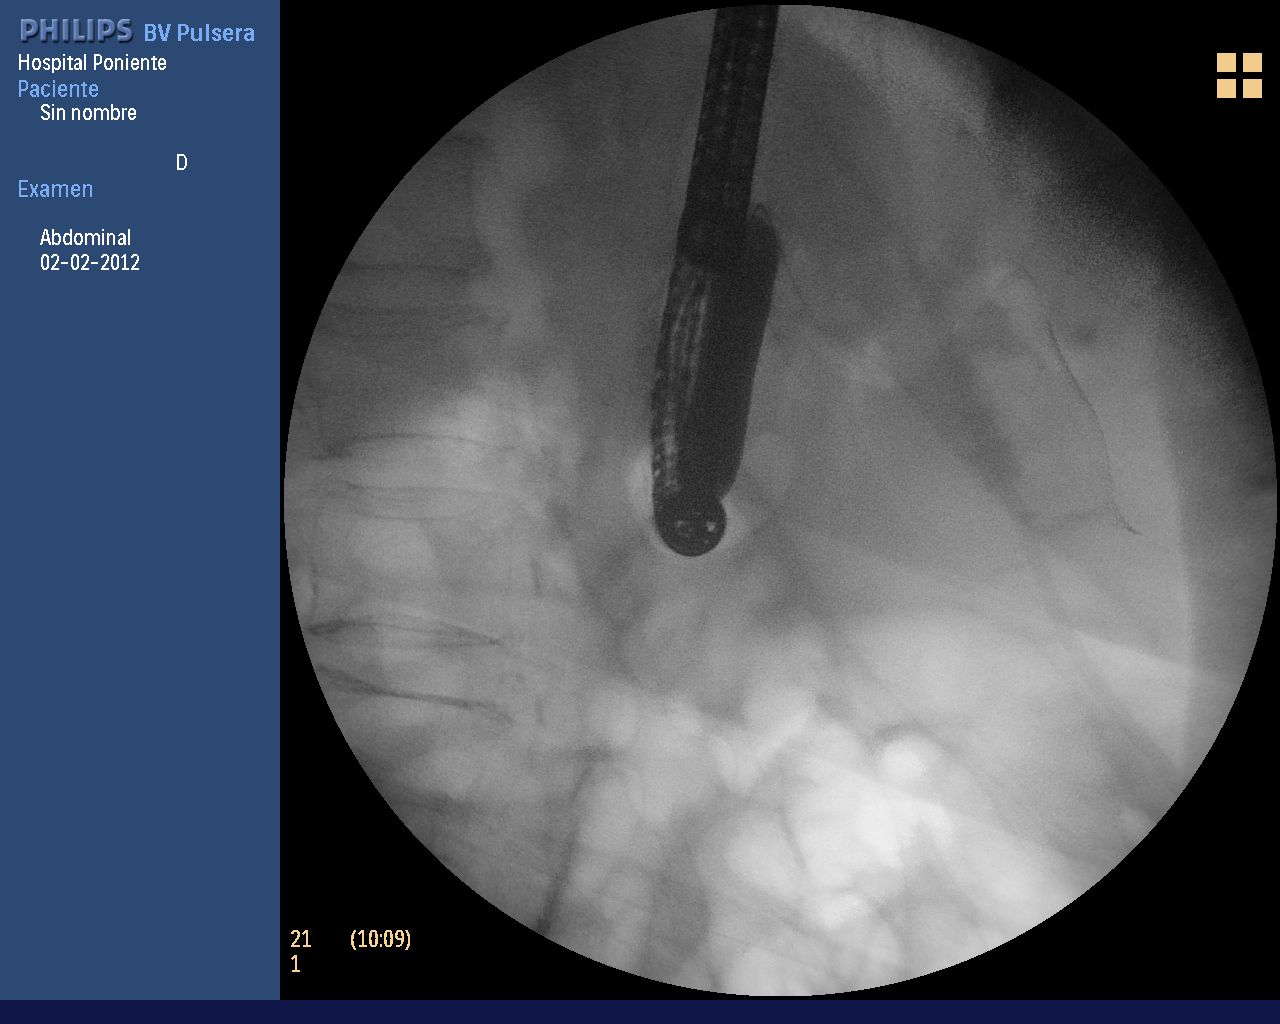

En el caso que aquí se presenta, debido a la poca experiencia que tenemos en este tipo de pacientes, se decidió colocar una prótesis biliar en la primera CPRE para solventar la colangitis. En un 2º tiempo, la realización de una esfinterotomía de aguja sobre dicha prótesis (que aporta gran seguridad al corte) y una posterior esfinteroplastia, consiguieron completar el procedimiento.